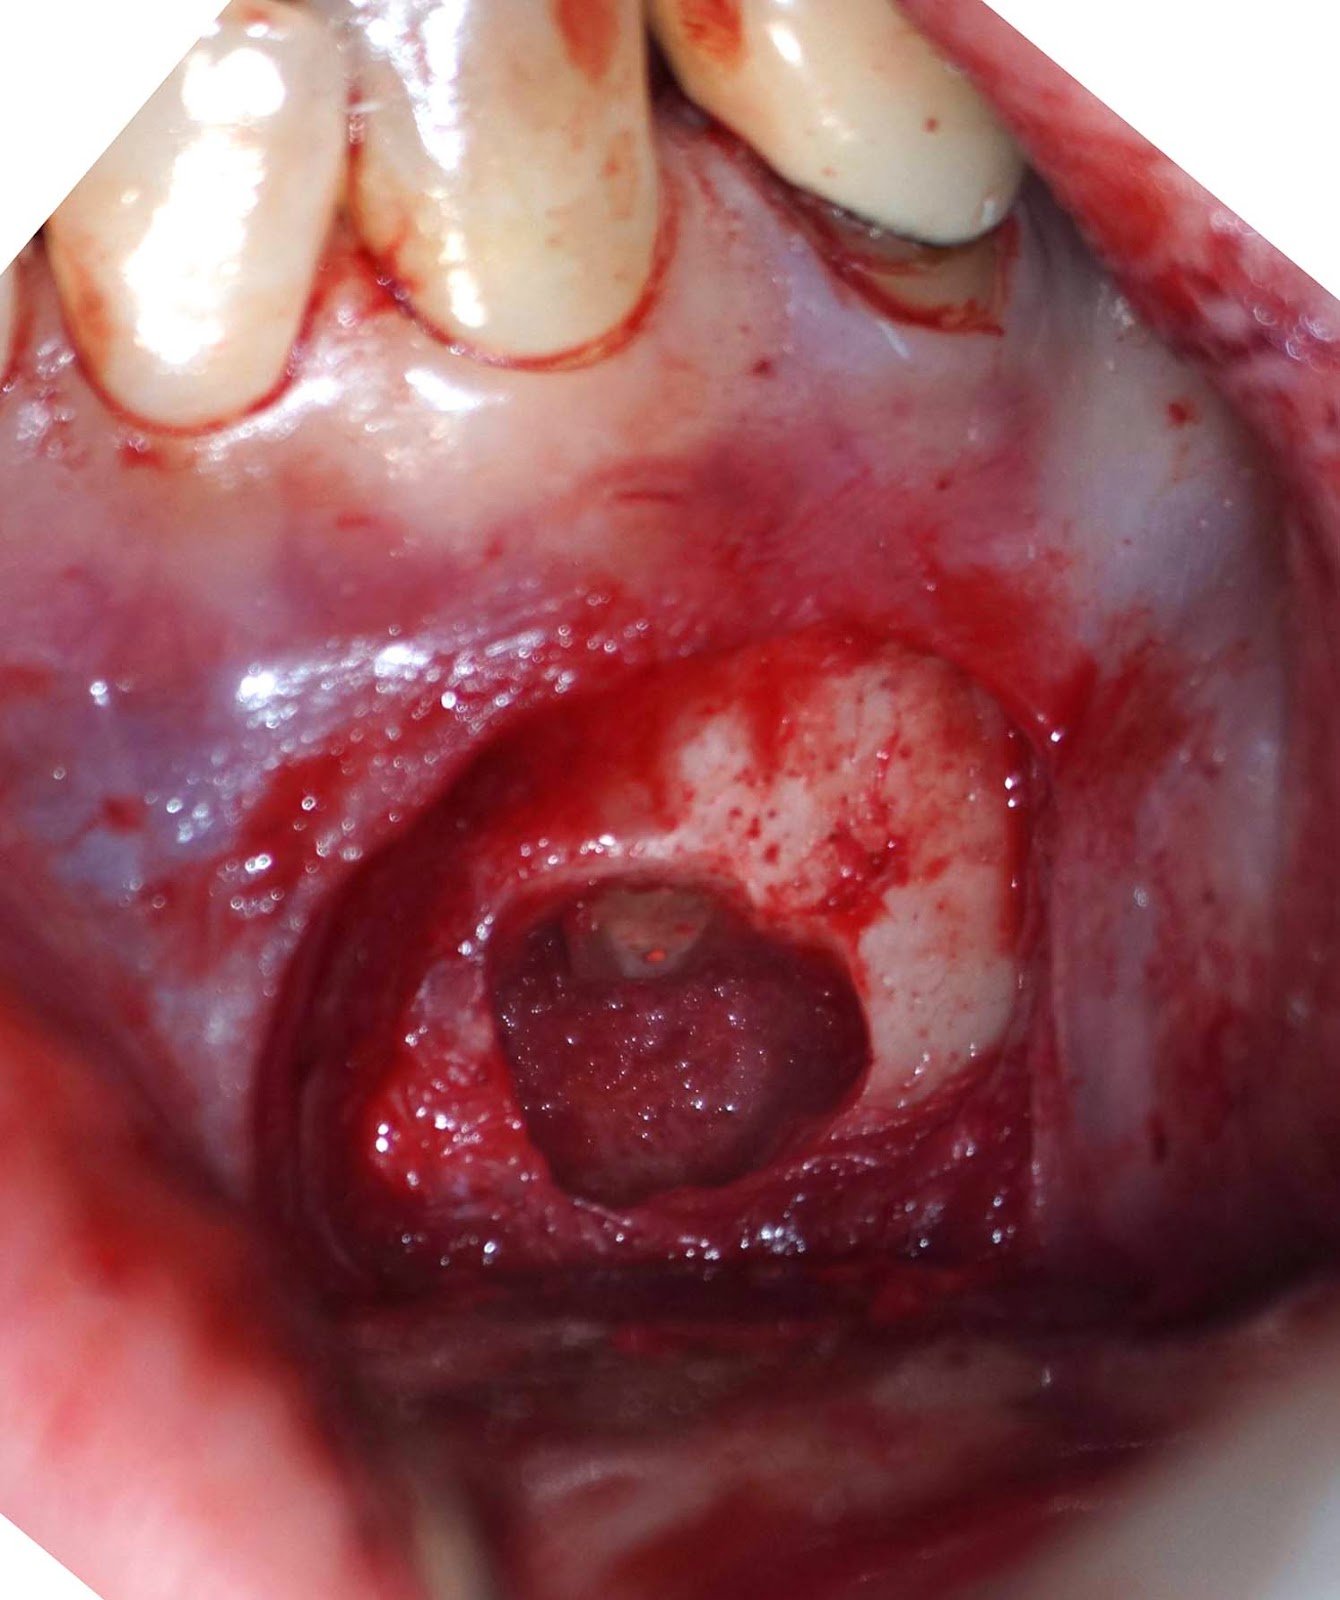

DX: Prior RCT with possible periapical cemental dysplasia. Apical surgery recommended with biopsy.

Biopsy report indicated Periapical Cemental Dysplasia (anterior focal osseous dysplasia) Recurrence would be unusual, but other areas of dysplasia can arise as well as truamatic bone cysts are also common.